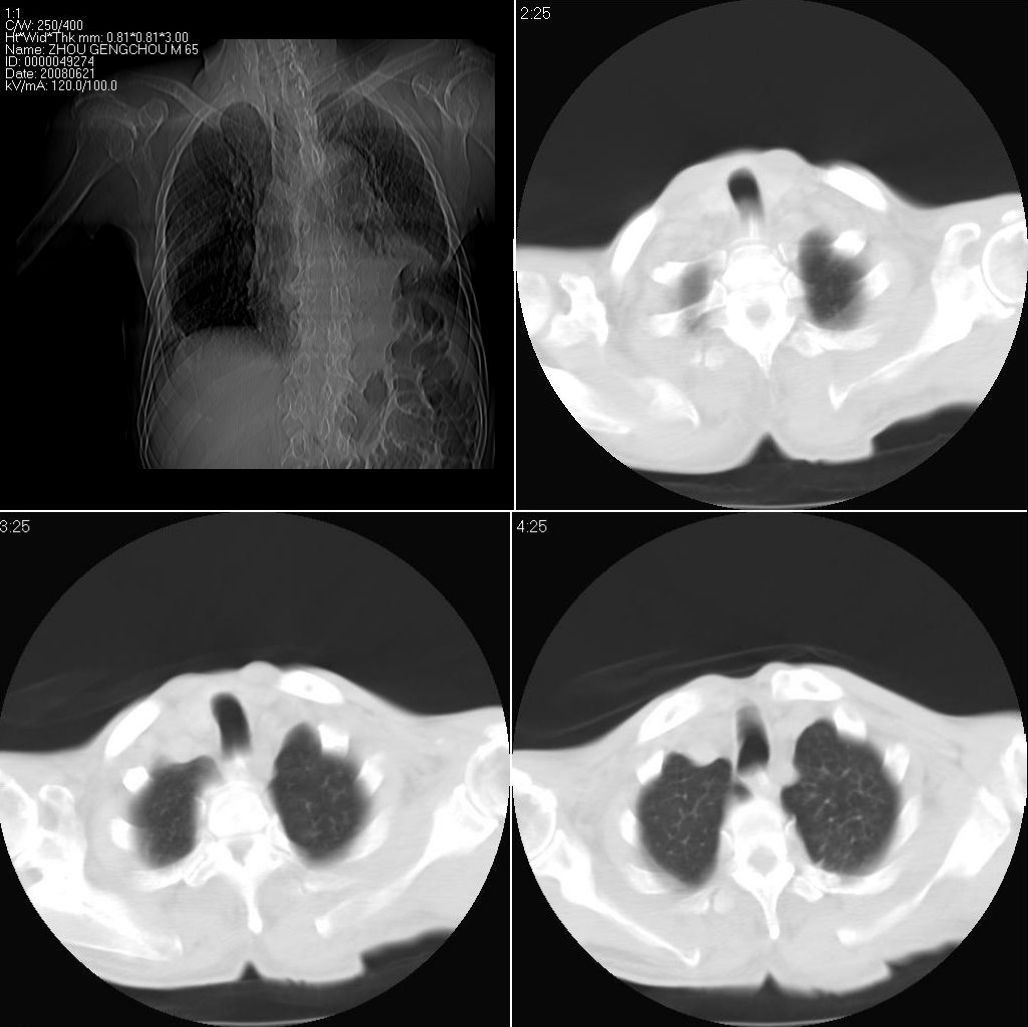

男性,65岁。因外伤来诊。该患者因脑外伤住院。以下是今天的dr和ct:

一周前胸片无异常,不考虑肿瘤,现x片及ct表现应与外伤有关,考虑左侧外伤性膈疝,并左下肺不张。右肺挫裂伤。少量胸水。

一周前胸片无异常,不考虑肿瘤,现x片及ct表现应与外伤有关,考虑左侧外伤性膈疝,并左下肺不张。右肺挫裂伤。少量胸水。支持

1 外伤性左侧膈疝、胸腔积液致左肺下叶不张 2右肺挫伤

右侧第7肋骨腋段骨折并右肺挫伤;左侧膈疝并肺不张。